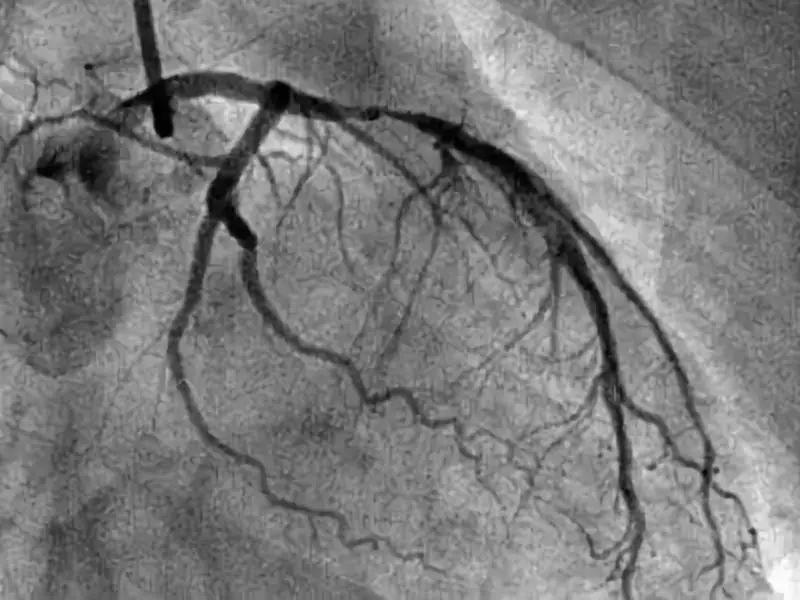

冠脉造影检查,是一种针对冠心病检查的重要方法,它的有效率非常高,能准确且清晰的显示患者冠状动脉的解剖结构以及它可能存在的畸形、阻塞性位置,是目前唯一也是最先进的心血管检查方式。

冠脉造影,有一项是看患者的冠脉血流分级:

0级,无灌注,患者冠脉闭塞部位及远端无造影剂充盈。

1级,造影剂通过闭塞部位,但是远端血管无造影剂。

2级,造影剂能抵达远端血管,但是速度缓慢。

3级,造影剂快速抵达远端血管。

通过分级,可以一定程度判断狭窄程度。另外,医生建议如果你要去做冠脉造影,前一天一定要做好准备,首先要休息好,以免在做冠脉造影时出现意外。